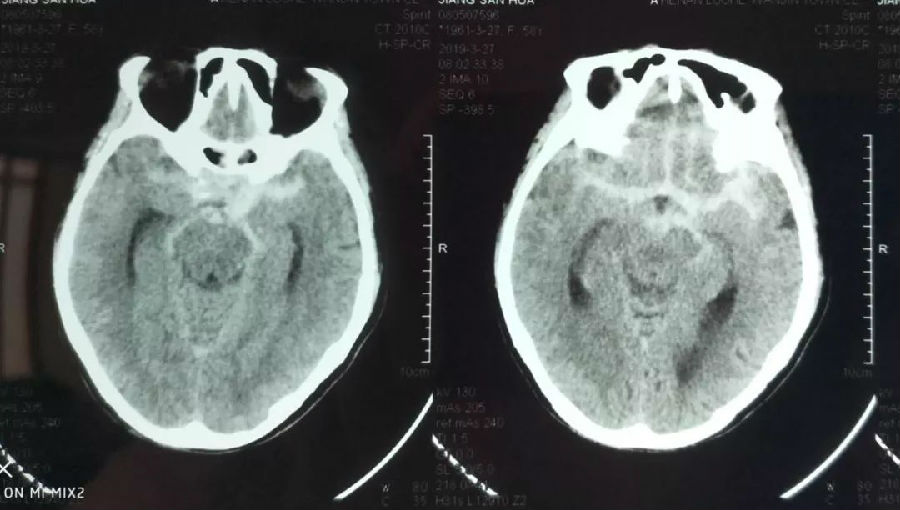

事情发生在3月27日,患者江女士(化名)早上起床后突感头痛,并伴随呕吐,视物成双、言语不清、肢体麻木无力抽搐、意识丧失、大小便失禁等,家人发现后立即送往当地镇医院,行头颅CT提示“蛛网膜下腔出血”,为求进一步治疗,家人急忙将患者转入市中心医院,考虑到颅内动脉瘤的可能,医院按照脑卒中治疗流程对患者进行急诊血管造影,检查结果证实为“前交通动脉动脉瘤破裂”。

▲头颅CT检查发现“蛛网膜下腔出血”